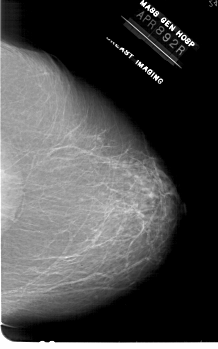

A_1862_1.LEFT_CC

LEFT_CC LINES 6871 PIXELS_PER_LINE 4516 BITS_PER_PIXEL 12 RESOLUTION 43.5 OVERLAY

FILE: A_1862_1.LEFT_CC.OVERLAY

TOTAL_ABNORMALITIES 1

ABNORMALITY 1

LESION_TYPE MASS SHAPE LOBULATED MARGINS CIRCUMSCRIBED

ASSESSMENT 4

SUBTLETY 2

PATHOLOGY BENIGN

TOTAL_OUTLINES 1